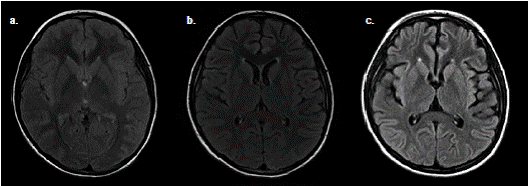

En el examen físico se evidenció afasia, lateralización de la marcha a la izquierda y disdiadococinesia izquierda. Durante la observación, se manifestaron movimientos bruscos con desviación oculocefálica a la derecha y postura distónica en las cuatro extremidades. La paciente se tornó estuporosa, lo cual motivó su ingreso en la unidad de cuidados intensivos pediátricos. La TC simple de cráneo, la RM cerebral simple (figura 2) y el electroencefalograma (EEG) inicial no evidenciaron alteraciones, pero el EEG posterior evidenció una lentitud en el rango delta difuso, y el examen citoquímico del líquido cefalorraquídeo mostró pleocitosis polimorfonuclear (cuadro1).